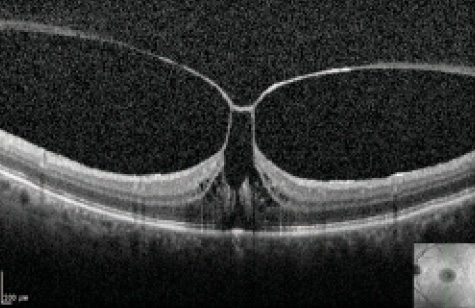

Over an observation period of approximately 1 year, we found that 21 of 61 (35%) patients experienced VMT resolution and 40 of 61 (65%) did not. Patients with spontaneous release of VMT were significantly more likely to have only inner retinal distortion (P = .01; Figure 1). VMT with solely inner retina disruption is commonly referred to as possessing the column sign, owing to the outer retina being undisturbed in the configuration of two columns (Figure 2). Patients with VMT involving both the inner and outer retina (Figure 3) were unlikely to have spontaneous release of their retinal distortion.

Figure 2. SD-OCT scan of a patient with VMT depicting the column sign. There is a focal area of abnormal adhesion resulting in VMT distorting the subfoveal and perifoveal inner retina. The outer retina remains intact and resembles two columns (white arrows). Note the intact external limiting membrane and continuous ellipsoid zone.